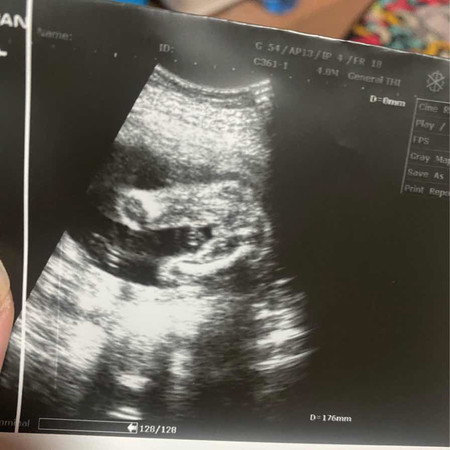

สอบถามเพศลูก

แม่ๆช่วยดูทีค่ะน้องเป็นผู้ชายหรือผู้หญิงคุณหมอก็บอกไม่ได้หมอบอกว่าชาย50หญิง50 แต่แม่แอบลุ้นผู้หญิงอยากมีลูกสาวมากค่ะ🥰

เห็นไม่ชัดค่ะถ้าแม่อยากได้ลูกสาวรอบหน้าที่มีนัดตอนซาวด์ลองให้คุณหมอดูอีดครั้งหนึ่งถ้าเป็นผู้หญิงจะเป็นกลีบๆไม่มีอะไรยื่นหรือโผล่ออกมาค่ะแต่ถ้ามีอะไรยื่นออกมาแสดงว่าน้องเป็นผู้ชายค่ะ ขอให้คุณแม่สมหวังค่ะ🥰

หมอบอกไม่ได้เท่ากับยังไม่ชัดเจนค่ะ บางที่อาจเป็นสายสะดือในกรณีที่เป็นเพศหญิง